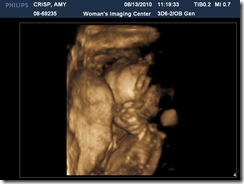

it’s a……..girl!!!

we went last friday to find out if little e will have a baby brother or baby sister.  we were super excited to find out this little one will be a girl {although we honestly would have been soooooo excited either way!}

i don’t think any of these pictures show it very clearly but we got one shot that they printed out that made it VERY obvious so i am fairly confident that she truly is a girl :)

her feet & tooshie :)

like i said, not obvious to me but we do have a printed out picture where it is :)